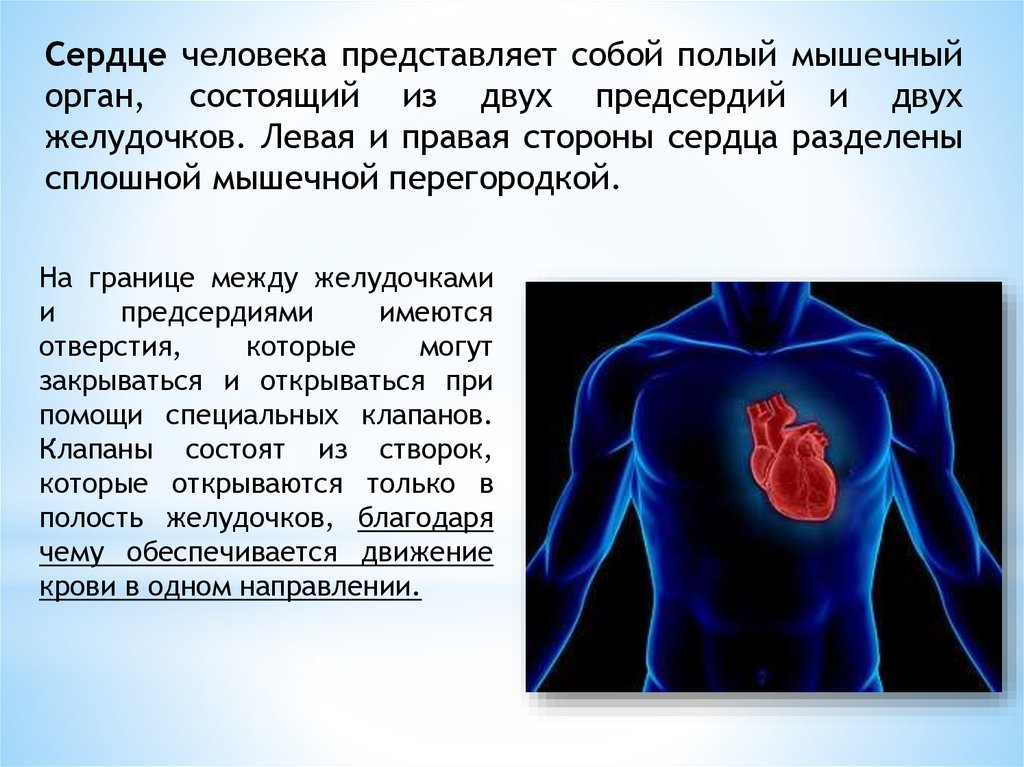

Сердце у человека располагается в грудной полости.

Расположение сердца у человека.

Анатомическое расположение сердца.

Сердце в грудной клетке расположено.

Где расположено сердце у человека анатомия.